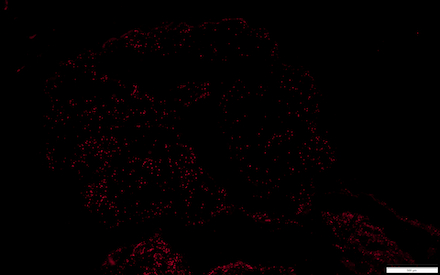

Methods: We selected markers for each of the components of NETS: (1) a granule protein, myeloperoxidase (MPO), (2) citrullinated histone 3 (CitH3), and cellular nucleic acid (NA, using Hoechst 33342). This was a single-blind study using cryopreserved thrombi from 30 patients, 15 with AF. Stroke thrombi were collected over a two-year span, and immediately frozen to -80*C post-thrombectomy. To capture the coverage of NET markers more comprehensively for each patient, we used cryostat to sample four sections (five-micron thickness) from each thrombus. We then fixed sections with 4% formaldehyde in phosphate buffered saline (PBS), performed immunohistological staining, and quantified extent of staining using ImageJ. Data for each NET marker from a single thrombus is represented as the mean percentage of thrombus area staining positively across the four corresponding sections. After performing Shapiro Wilks test for normality, statistical comparisons of NET marker staining coverage between AF and non-AF thrombi were performed with either unpaired T test or Mann-Whitney U test, depending on whether a parametric or non-parametric test was appropriate.

Results: Thrombi from patients with AF had greater MPO coverage(17.9 +/- 1.47% versus 11.6 +/- 1.29% in non-AF, p<0.01) and CitH3 coverage(12.6 +/- 1.46% versus 7.4 +/- 1.11% in non-AF, p<0.01). Staining for nucleic acid with Hoechst 33342 trended toward higher coverage in AF but did not reach significance (27.8 +/- 3.35% versus 22.6 +/- 3.20% in non-AF, p=0.30).